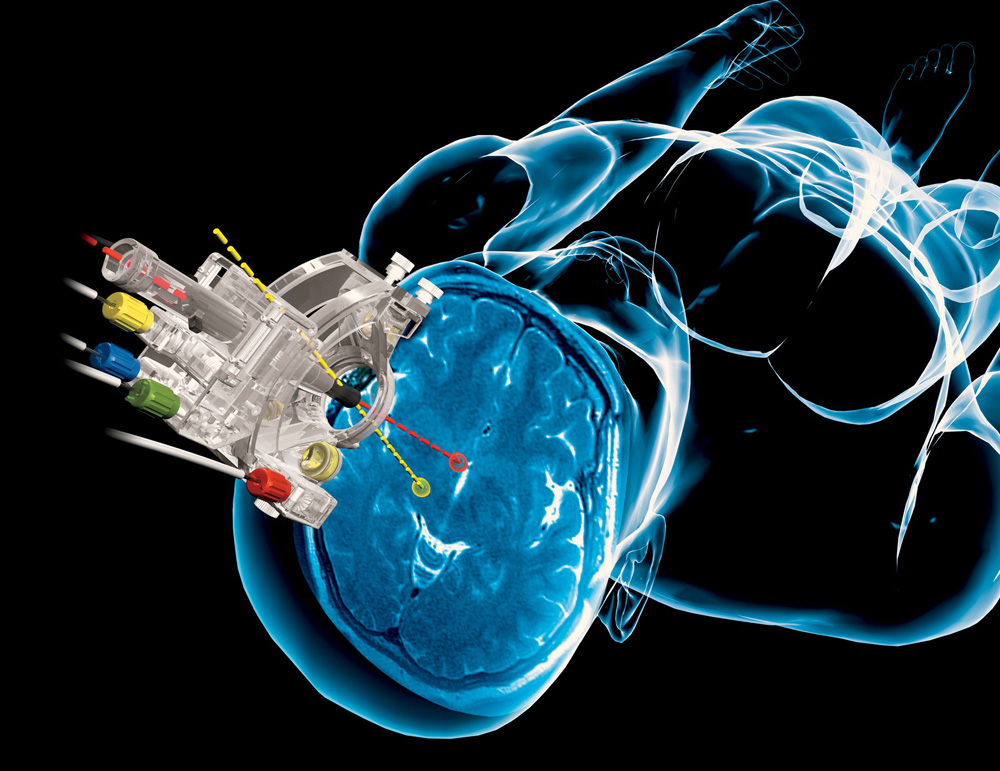

我院筹建山东省肿瘤微环境与分子影像重点实验室通过专家论证

中国首家|我院与尼康共建肿瘤微观成像创新中心